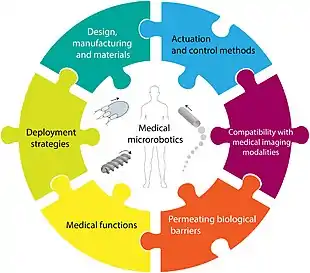

Already in 2010, Nelson et al. reviewed the existing and envisioned applications of microrobots in minimally invasive medicine.[187] Since then, the field has grown, and it has become clear that microswimmers have much potential for biomedical applications.[1] Already, many interesting tasks can be performed in vitro using tailored microswimmers. Still, as of 2020, a number of challenges regarding in vivo control, biocompatibility and long-term biosafety need to be overcome before microswimmers can become a viable option for many clinical applications.[188][1]

A schematic representation of the classification of biomedical applications is shown in the diagram on the left below. This includes the use of microswimmers for cargo transport in drug delivery and other biomedical applications, as well as assisted fertilisation, sensing, micromanipulation and imaging. Some of the more complex microswimmers fit into multiple categories, as they are applied simultaneously for e.g., sensing and drug delivery.[1]

The design of an untethered microscopic mobile machine or microrobot to function in vivo with medical interventional capabilities should assume an integrated approach where design 3D body shape, material composition, manufacturing technique, deployment strategy, actuation and control methods, imaging modality, permeation of biological barriers, and the execution of the prescribed medical tasks need to be considered altogether, as illustrated in the diagram on the right above. Each of these essential aspects contains a special design consideration, which must be reflected at the physical design of the microrobot.[189]